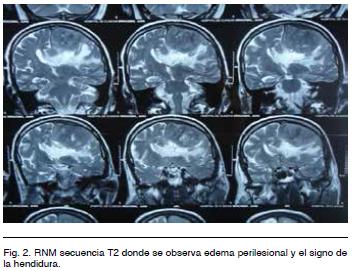

En T2 se observa isointenso, identificándose liquido cefalorraquídeo entre el tumor y el cerebro (signo de la hendidura). Se ve también importante edema perilesional digitiforme (Figura 2).

Con respecto a los estudios de imagen, es de elección la IRM de cráneo. Como ya se mencionó, estos tumores son imagenologicamente similares a los meningiomas, lo que hace difícil el diagnóstico preoperatorio. Se han descrito algunas características particulares que nos pueden sugerir y orientar hacia un HPC como son: 1) un contorno tumoral polilobulado con base de implantación dural más estrecha, 2) con la administración de contraste hay realce intenso pero heterogéneo, 3) en la secuencia T2 se pueden ver imágenes de vacío de flujo intratumoral, 4) habitualmente no presentan hiperostosis, en cambio producen erosión ósea en mas del 50% de los casos, 5) no tienen calcificaciones intratumorales, 6) la espectroscopia podría diferenciar los HPC de los meningiomas, se ha sugerido que altos valores de mioinositol se pueden encontrar en los primeros4,10.